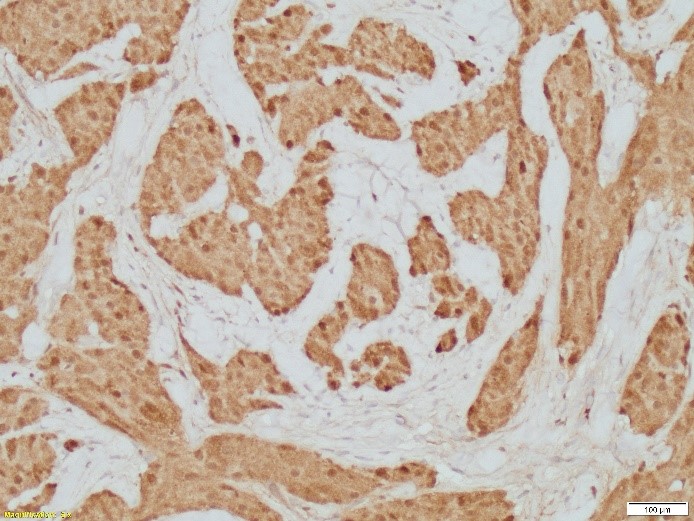

On microscopic exam, GCT has an infiltrative growth pattern composed of sheets, clusters, and trabeculae of large, round to polygonal cells with abundant, eosinophilic, and distinctly granular cytoplasm. Their granular cytoplasm is the results from cytoplasm accumulation of secondary lysosomes.

The diagnosis of granular cell tumor is usually straightforward. In the breast, the differential diagnosis is with carcinomas (particularly apocrine carcinomas) given the epithelioid appearance of the cells and the frequent presence of perineural and perivascular involvement in otherwise benign granular cell tumor.

By immunohistochemistry, GCT can be distinguished from carcinomas, since they are negative with keratins and show strong and diffuse S-100 protein expression. Caution should be exercise in only consider S100 as standalone stain, since some breast carcinomas can be positive with this marker. Ultimately, the cytomorphology with nuclear atypia and mitosis in carcinomas, help in the differential diagnosis.